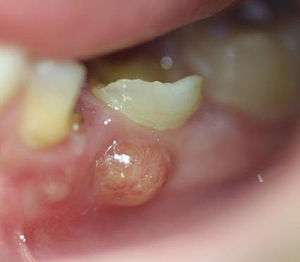

![]() | |

| A decayed and broken down tooth, which has undergone pulpal necrosis (death of the tooth pulp). A periapical abscess (i.e. around the apex of the tooth root) has then formed and pus is draining into the mouth via an intraoral sinus (colloquially termed a gumboil). | |